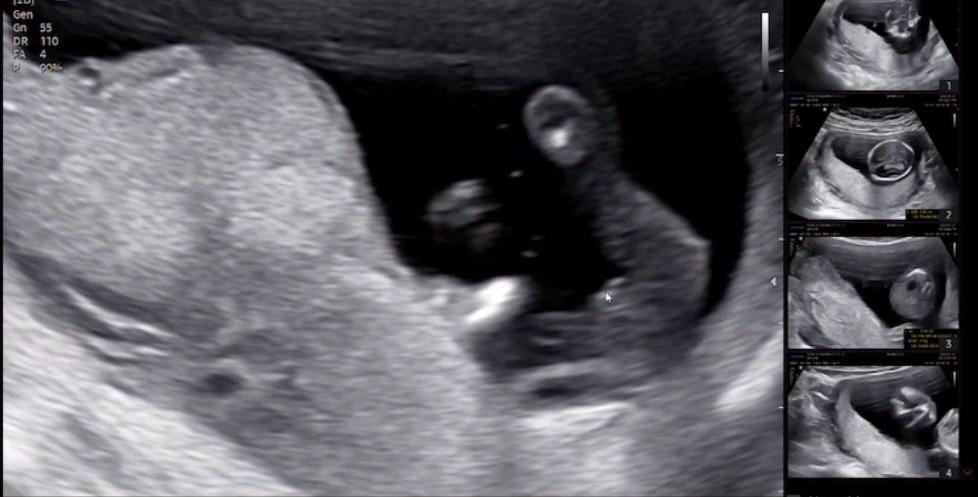

15주 성별

오늘 궁금한거 물어볼겸 이르게 성별 보러갔는데 선생님이 마우스로 가르키시면서 매끈하다고 여아 7~80%정도 확실한거같다 다음주에 오면 99%확정 시켜주시겠다 했는데 여러분들 보시기엔 어떠세요?? ㅠㅠ 딸 확정일까요?